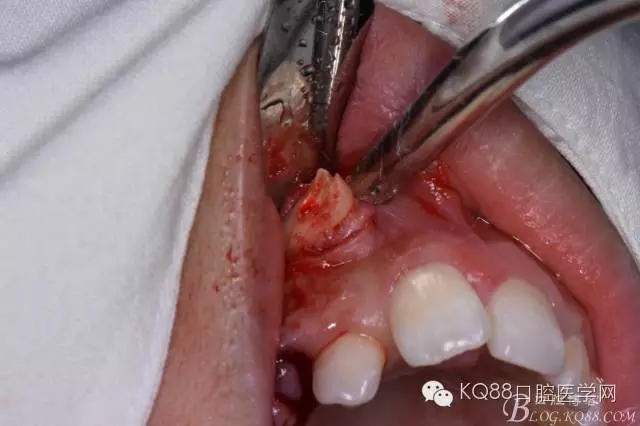

圖6.去骨

圖7.暴露出13牙冠

圖8.高速渦輪機(jī)分牙、目的是盡量少去骨。

圖9. 從頸部截分13